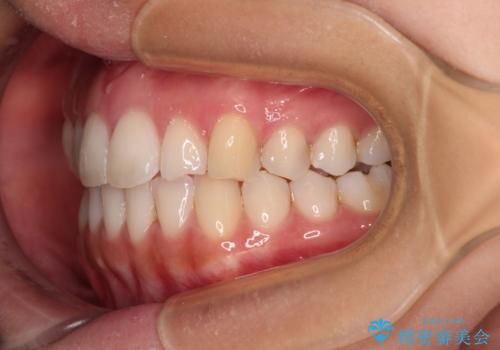

前歯の重なりをインビザライン・モデレートで矯正治療

- 上下前歯の重なりを気にして来院された患者様です。

安価なインビザラインパッケージを用いての治療を希望されており、デコボコの程度が中等度であったため、インビザライン・モデレートを用いて矯正治療を行うこととしました。